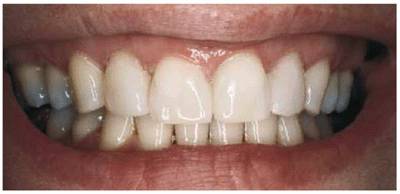

PROBLEM: This 60-year-old airline travel agent presented with a large

diastema of the maxillary central incisors (see Figures 23-10A, and 23-10E). Advanced cervical erosion was

Figure 23-10A: This 60-year-old woman presented with a large diastema between her central incisors and cervical erosion on her maxillary anterior teeth.

TREATMENT: The teeth were slightly reproportioned by stripping and

disking the distal surfaces of the central and lateral incisors (see Figure 23-10B). The key to successful restorative

diastema closure is creating the illusion of a believable "natural"

tooth width in the central and lateral incisors. Figure 23-10C shows a narrower width of the

central incisors after the distal surfaces have been sufficiently reduced and

ready for full-veneer bonding to close the central incisor diastema and restore

the cervical defects. Final restoration is seen in Figure 23-10D

RESULT: Figure 23-10F shows an entirely new smile with

better proportioned teeth rather than two oversized teeth. Note that the

cervical erosion on the maxillary right side has been simultaneously restored

with composite resin bonding. The mandibular anterior incisors were also

cosmetically contoured to give them a level plane of occlusion. Comparing the

before and after smiles (see Figures 23-10E

and F)

specifically illustrates how the patient's mid-upper lip naturally drops rather

low, forming a "cupid's bow." This lowered lip line tends to mask the

extra width of the central incisors, which also contributes to the illusion.

Figure 23-10E and F: Comparison of the before and after smiles shows an entirely new smile that is better proportioned by treating four anterior teeth. If only the two central incisors had been bonded, two oversized central incisors would have resulted.